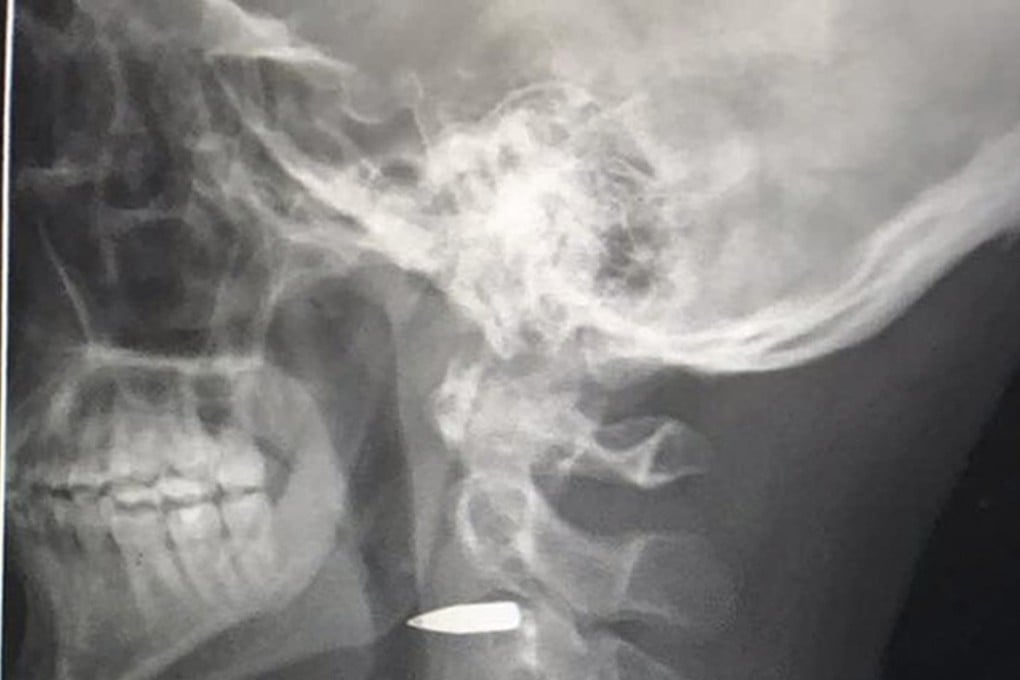

“Thanks everyone – I’m okay. Bullet is still in my neck, but it missed everything important,” Harvey tweeted. Dr Jose Eric Laya said the bullet was lodged below Harvey’s left ear.